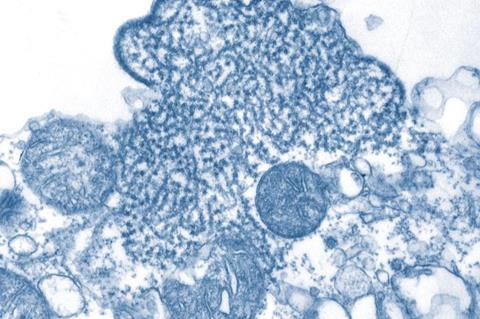

Researchers at the Wuhan Institute of Virology have decoded a critical survival strategy of the deadly Nipah virus (NiV), identifying a key host protein hijacked by the pathogen and translating this discovery into a promising new treatment approach. The work, published in Protein & Cell, addresses the urgent need for therapies against this high-mortality virus, for which no specific drugs currently exist.

Niv is a highly pathogenic zoonotic virus that causes acute encephalitis in humans, with a mortality rate ranging from 40% to 75%. In 2018, it was listed on the WHO R&D Blueprint as a virus capable of causing a severe international epidemic.

Due to stringent research constraints, including the requirement for biosafety level 4 (BSL-4) laboratories, the molecular mechanisms underlying NiV replication remain poorly understood, and no effective vaccines or antiviral treatments have been developed.